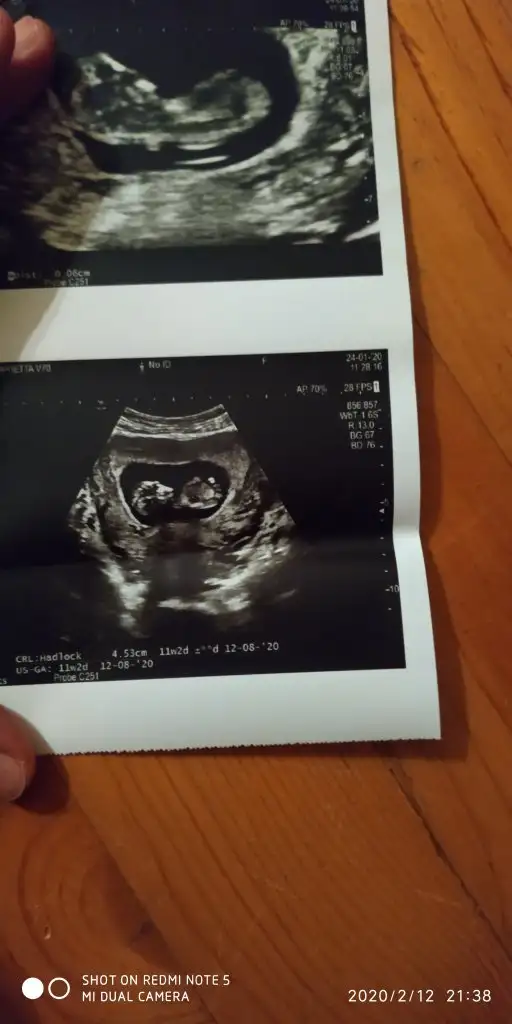

dr soylemeden siz gorun genital nub teorisi ( bebegin cinsiyeti)

Ikra meyra Ikra meyra merhaba canım banada yardımcı olur musun cok merak edıyorum